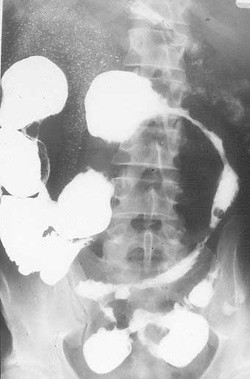

Malattia di Crohn

La malattia di Crohn è una patologia infiammatoria cronica dell'apparato digerente a causa ancora sconosciuta che interessa più frequentemente il tratto terminale dell'ileo e la valvola ileociecale anche se ne possono essere colpiti la bocca, lo stomaco, tutto l’ileo ed il colon. Provoca spesso la formazione di ascessi, fistole e ragadi anali che devono essere trattati in modo diverso rispetto a quelle primarie. Può associarsi a disturbi auto-immunitari a livello sistemico, come ulcere della bocca, uveiti e manifestazioni artritiche.

La malattia si può complicare con comparsa di occlusione intestinale, ascessi addominali, fistole enterocutanee (tra l’intestino e la cute) o tra l’intestino ed altri organi addominali (altri tratti di intestino, vescica, utero, uretere).

Se la terapia medica non è sufficiente a controllare i sintomi o compaiono complicanze (stenosi, fistole, ascessi, perforazioni) è indispensabile il parere di un coloproctologo esperto che possa indicare il trattamento chirurgico più adatto per risolvere l’urgenza e riportare il quadro clinico in uno stato di quiescenza, è’ evidente che l’intervento varia a seconda della situazione clinica. Per questo il chirurgo deve essere un esperto della patologia dovendo valutare volta per volta l’utilità di eseguire resezioni intestinali, allargamenti di stenosi, trattamenti di fistole, resezione di altri organi addominali o deviazioni intestinali (stomie). La cautela nell’esecuzione dell’intervento è indispensabile perché è noto che nella malattia di Crohn nessuna terapia porta alla guarigione, anche se dopo la chirurgia il paziente può rimanere asintomatico per molto tempo.

Vedi immagine